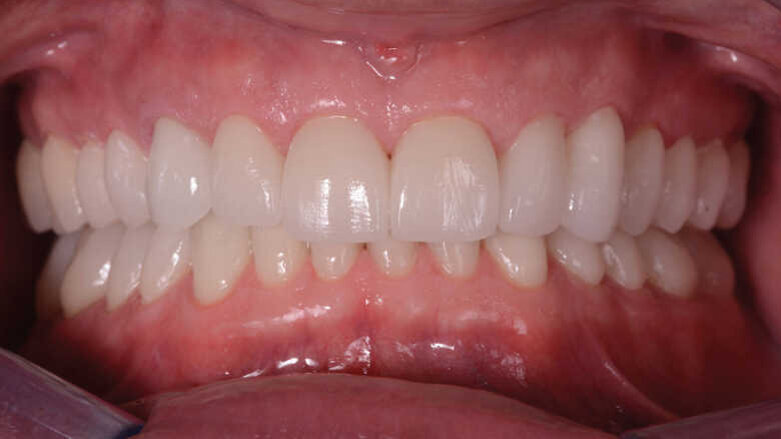

Figs. 13 et 14 : Photographies intraorales après le traitement.

Après l’élimination de l’excès de colle composite, l’occlusion est adaptée et vérifiée à l’aide du système d’évaluation occlusale T-Scan (Tekscan). Une contention amovible en résine acrylique est utilisée pour protéger les restaurations définitives, et celles-ci sont vérifiées six mois plus tard. À ce moment, les restaurations sont toujours stables et ne présentent aucun signe de fracture (Figs. 13–15). Le patient déclare également qu’il n’a plu souffert de maux de tête grâce à cette nouvelle dimension verticale d’occlusion.